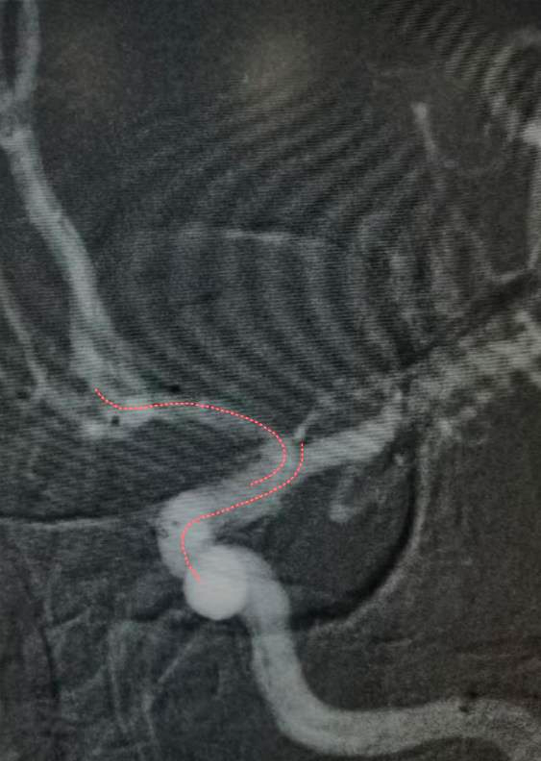

导丝“S”型塑形

我们看上面这个血管情况,血管比较粗,常规导丝单弯操作也很容易成功,但是导丝要术者用手旋转,如果塑形s型,就会更丝滑,看下面这个动态的图。

是不是很丝滑?